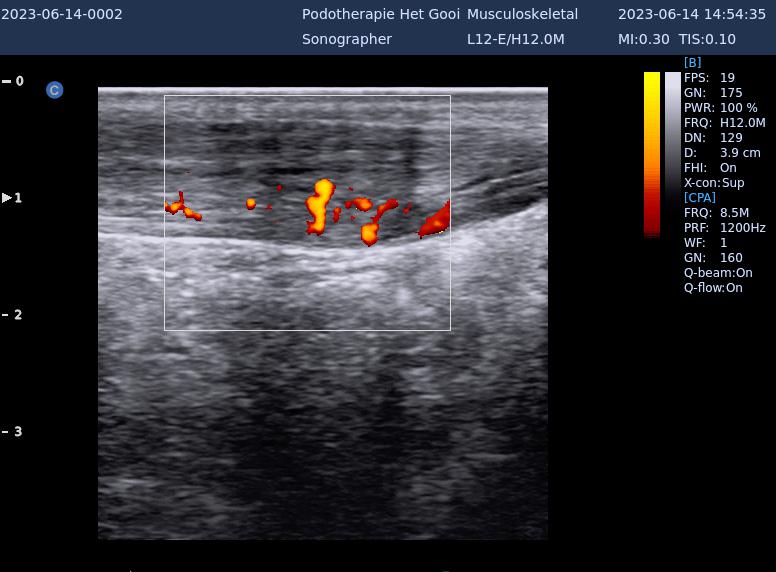

echo achillespees

Achillodynie (pijnlijke achillespees)

Pijnlijke Achillespees